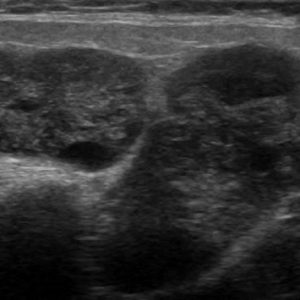

U tuyến nước bọt

Lượt xem: 160» 19-01-2021 -

U tuyến nước bọt

Lượt xem: 119» 18-01-2021 -

U tuyến nước bọt

Lượt xem: 152» 18-01-2021 -

U tuyến nước bọt

Lượt xem: 159» 18-01-2021 -